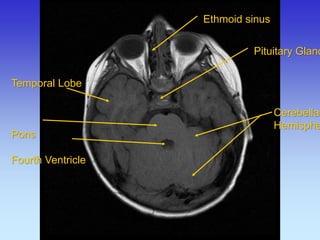

Ethmoid sinus

Cerebellar

Hemisphere

Pituitary Gland

Pons

Cerebellum

Temporal lobe

Fourth Ventricle